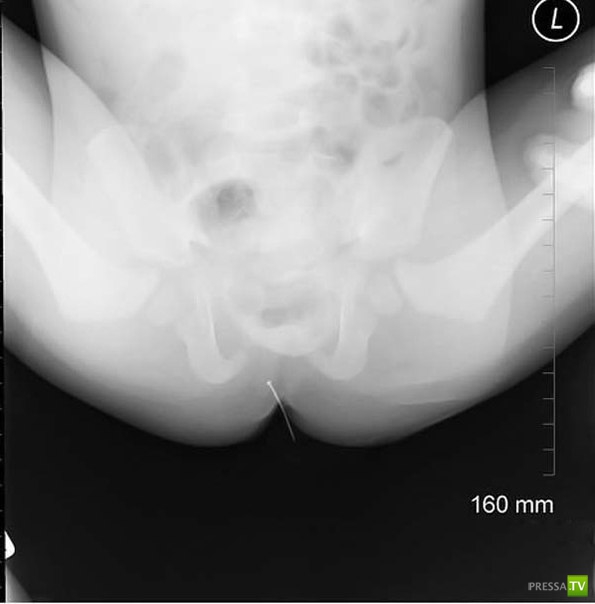

Маленький ребенок проглотил иголку. Она прошла через весь желудок и вышла там, где и должна была